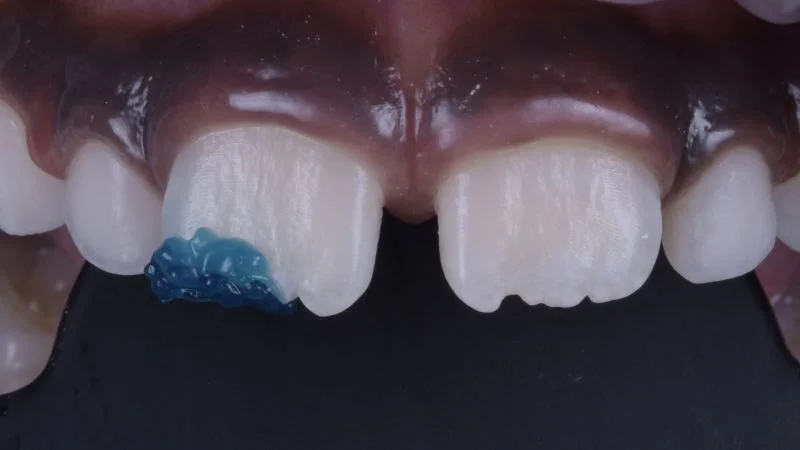

Ausgangssituation

Detailansicht der Oberkiefer-Frontzähne. Horizontale Kronenfraktur unter Einbeziehung der Inzisalkante sowie des distalen Anteils von Zahn 11.

Detailansicht des frakturierten Zahnes.

Ansicht von lateral.